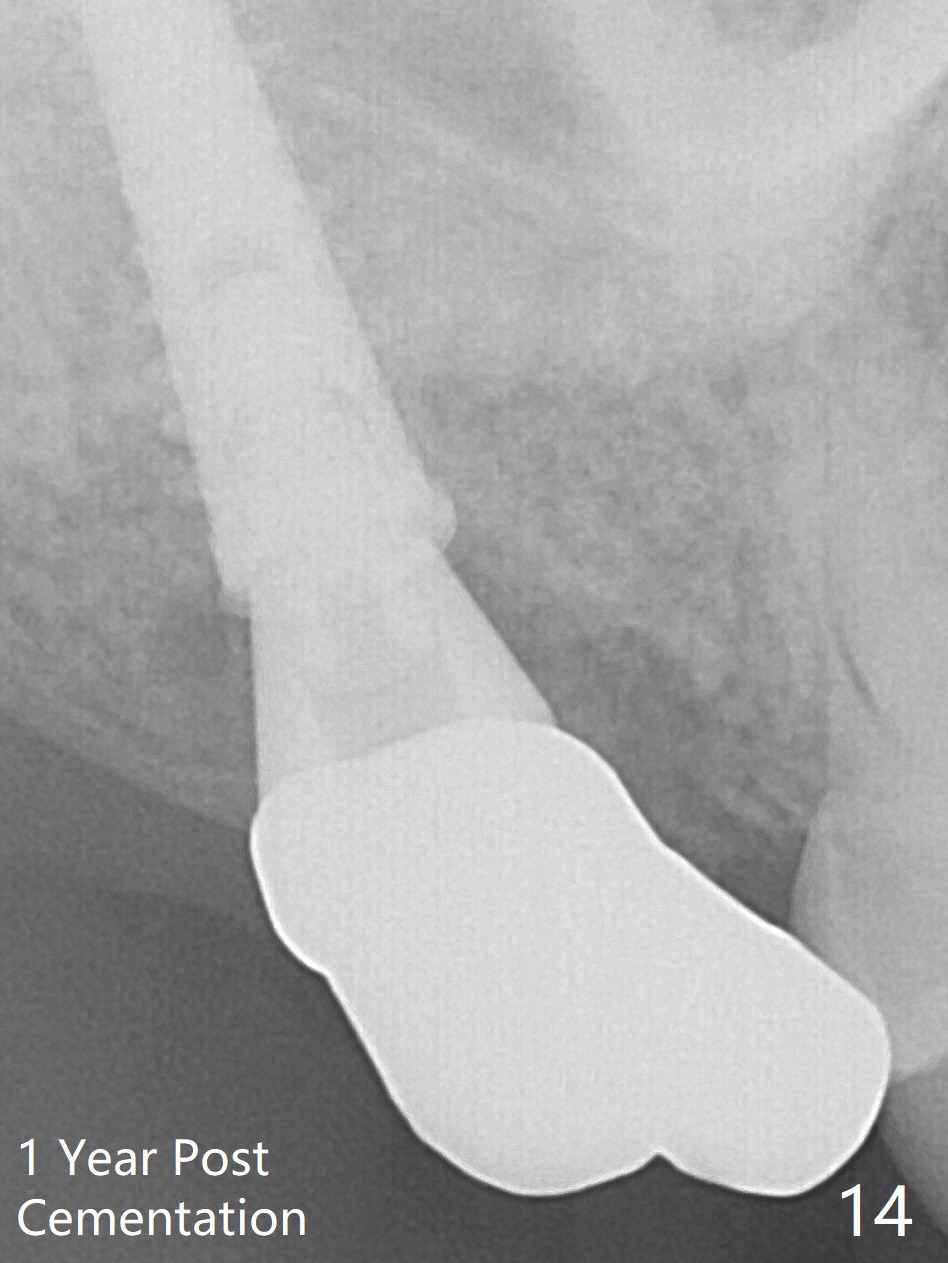

Fig.5 shows the mesial slope of the socket (M), which is more or less the center of the socket mesiodistally. If the osteotomy were set up in the red circle (Fig.6) in the mesial slope (Fig.8 green dashed line), the trajectory of 4.5x11 mm dummy implant (Fig.7) would be more ideal (Fig.8 red outline) with more native bone contact. Finally a longer IBS implant is placed (4.5x15 mm, Fig.9,10) to achieve primary stability (50 Ncm). When the provisional is removed for impression 3 months 10 days postop, the implant is found to have been placed distopalatally (Fig.13), which should have been avoided. It appears essential to use guide for a distal implant. It is agonizing to re-encounter the off-axial implant (Fig.14) and the distopalatal access hole (Fig.15) 1 year post cementation. It is also amazing that the abutment screw has not loosened. A fair-sized piece of bone graft has just been removed buccally (Fig.15,16). The patient complains of sensitivity 2 years 3 months post cementation, although there is no abnormality around the implant crown. Guided surgery is essential to avoid restoration complication. There is no thread exposure nearly 3 years post cementation; in fact the apical portion of the abutment is covered by the bone (Fig.17,18).